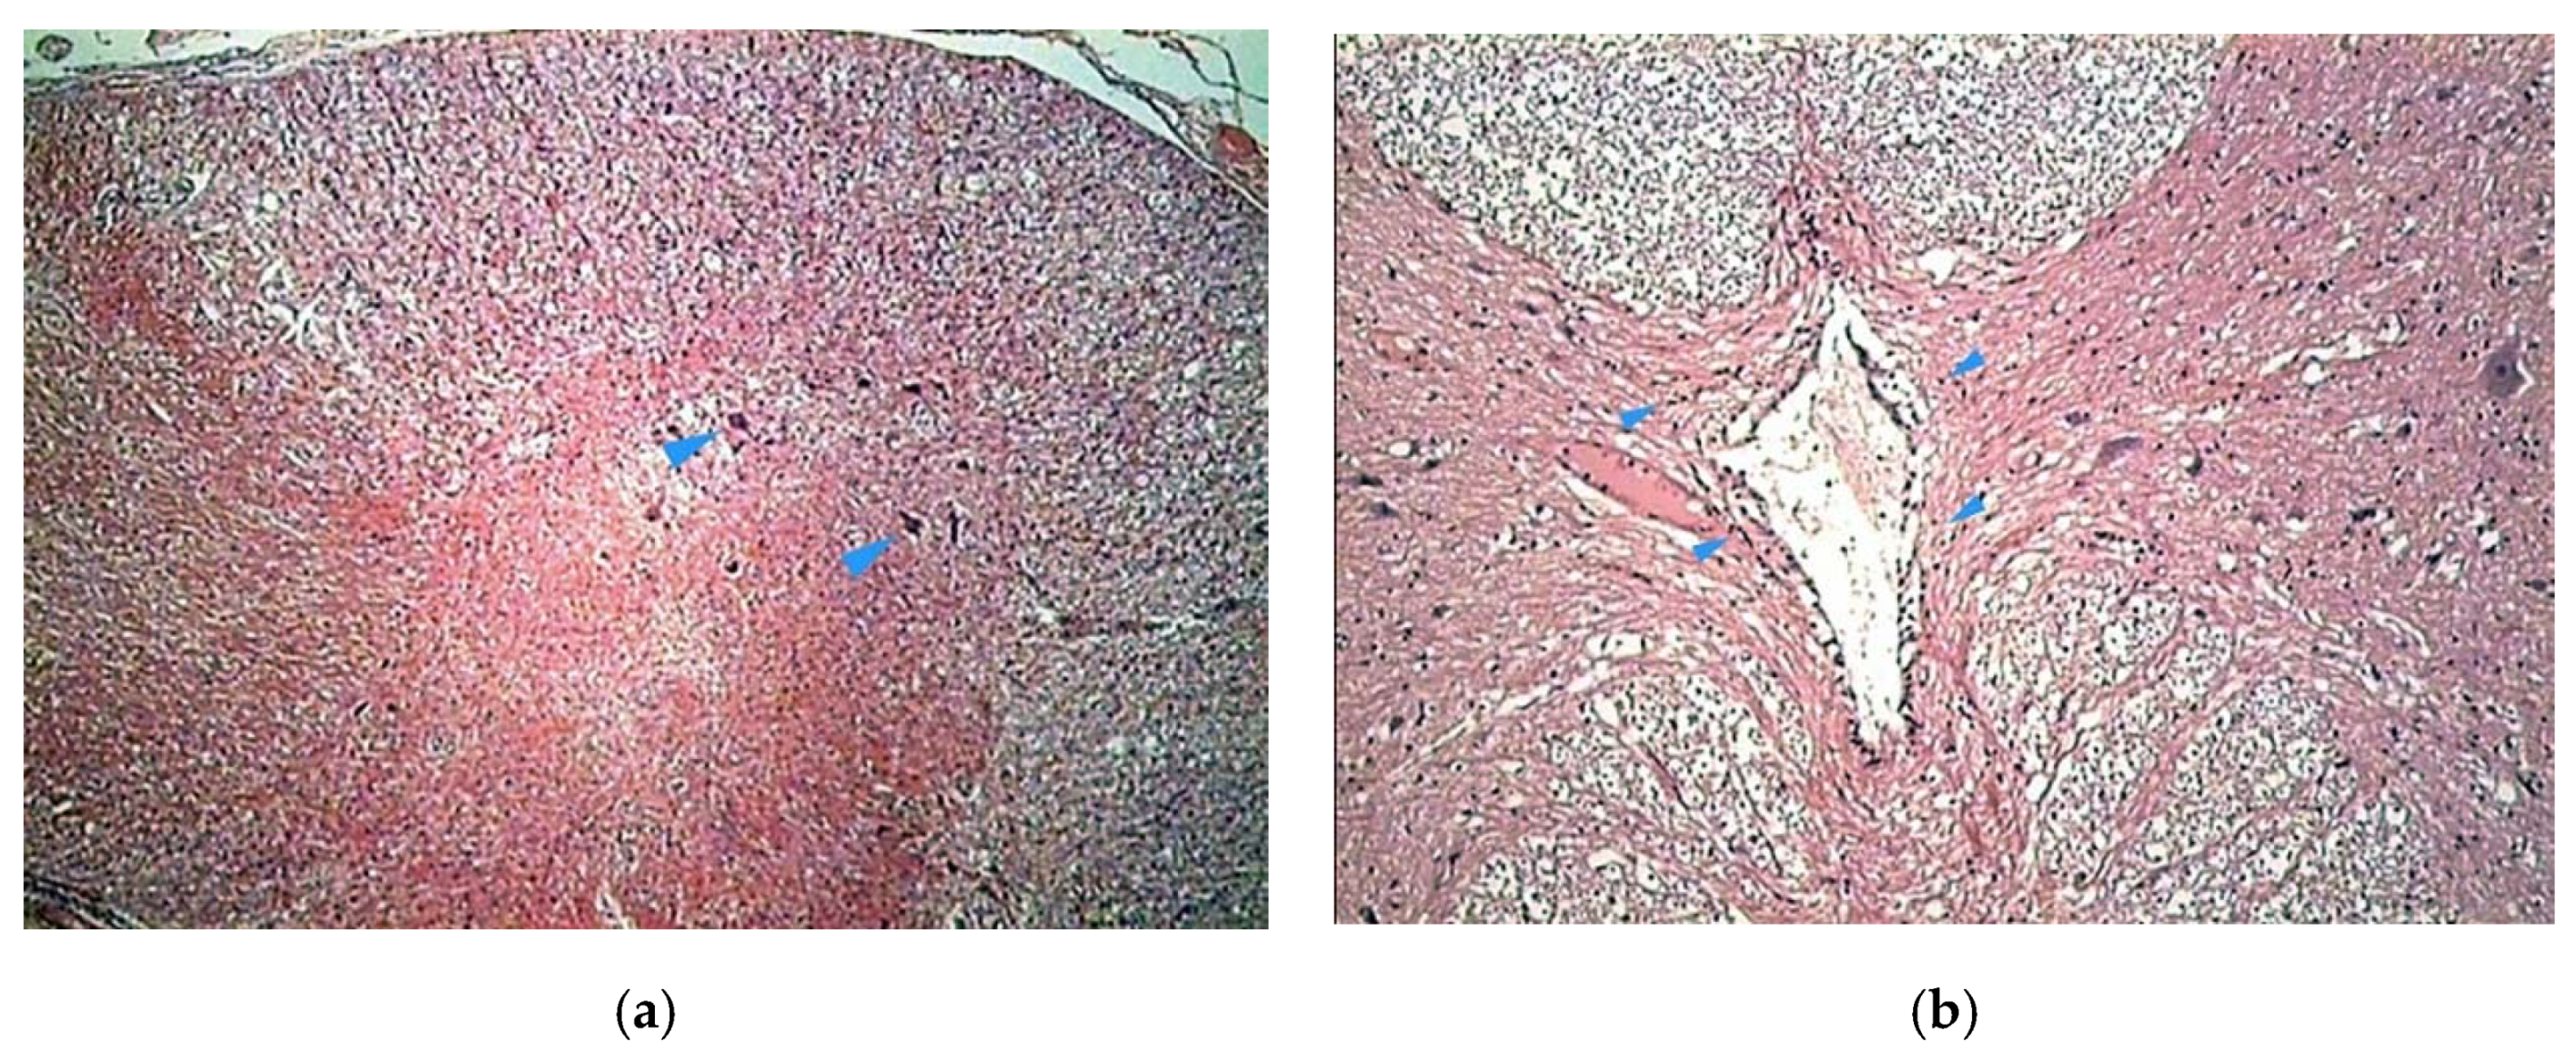

The histologic study on bony specimens at the osteotomized surface showed the presence of live osteocytes and osteoblasts in 92% of cases (Figure 2). Harvested spinal cord in 17 postmortem cases allowed to appreciate the anatomical integrity of both the dura and the neural tissue (Figure 3).

Figure 2.

Histologic study executed on a dog’s bone specimen. Hematoxylin–eosin 2.5X (a) and 10X (b), showing the presence of live osteocytes and osteoblasts near the osteotomized surface (arrowheads).

Figure 3.

Histologic study executed on a cat’s spinal cord. Hematoxylin–eosin 2.5X, showing the perfect anatomical integrity of the spinal cord and dura after piezoelectric osteotomy (a,b).